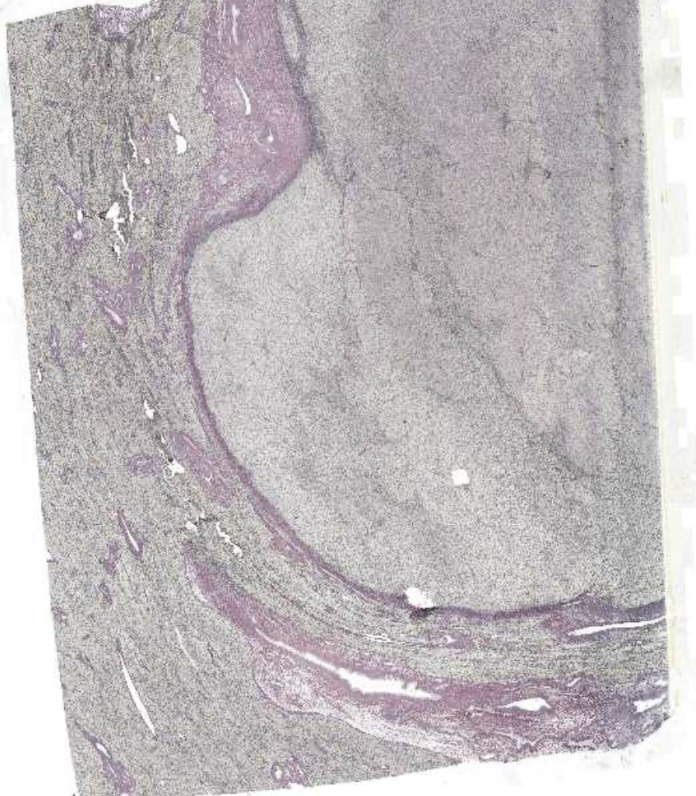

Liver with hepatocellular carcinoma

HCC - Tumor area

Surrounding areas are normal (has cells with lipofuscin in cytoplasm)

This area is a tumour surrounded by a capsule

Tumour area shows loss of normal sinusoid pattern

Normal structures can be seen amongst the tumour portion (e.g. bile ducts)

Enlarged nuclei (high nuclei/cytoplasm area)

No portal triads

Less pink, more blue → Enlarged nuclei + Immune cells

Nuclei are very close → Less cytoplasm

Large variations of nuclei size